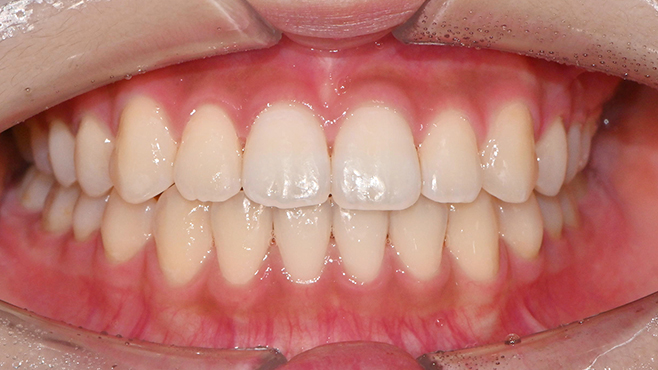

맞는 건 괜찮은데… 충치는 못 참겠습니다|20대 격투기 선수 치과 방문기

2026.02.06